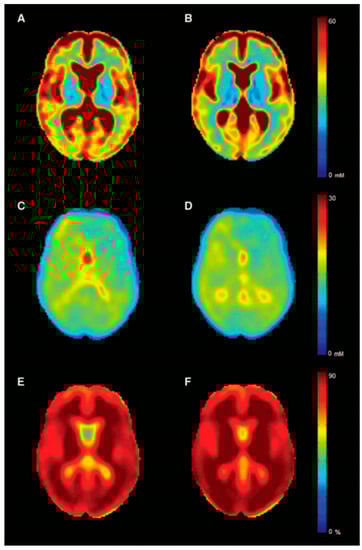

- Petracca, M.; Fleysher, L.; Oesingmann, N.; Inglese, M. Sodium MRI of multiple sclerosis. NMR Biomed. 2016, 29, 153–161. [Google Scholar] [CrossRef]

- Inglese, M.; Madelin, G.; Oesingmann, N.; Babb, J.S.; Wu, W.; Stoeckel, B.; Herbert, J.; Johnson, G. Brain tissue sodium concentration in multiple sclerosis: A sodium imaging study at 3 tesla. Brain J. Neurol. 2010, 133 Pt 3, 847–857. [Google Scholar] [CrossRef]

- Maarouf, A.; Audoin, B.; Pariollaud, F.; Gherib, S.; Rico, A.; Soulier, E.; Confort-Gouny, S.; Guye, M.; Schad, L.; Pelletier, J.; et al. Increased total sodium concentration in gray matter better explains cognition than atrophy in MS. Neurology 2017, 88, 289–295. [Google Scholar] [CrossRef] [PubMed]

- Paling, D.; Solanky, B.S.; Riemer, F.; Tozer, D.J.; Wheeler-Kingshott, C.A.; Kapoor, R.; Golay, X.; Miller, D.H. Sodium accumulation is associated with disability and a progressive course in multiple sclerosis. Brain J. Neurol. 2013, 136 Pt 7, 2305–2317. [Google Scholar] [CrossRef]

- Zaaraoui, W.; Konstandin, S.; Audoin, B.; Nagel, A.M.; Rico, A.; Malikova, I.; Soulier, E.; Viout, P.; Confort-Gouny, S.; Cozzone, P.J.; et al. Distribution of brain sodium accumulation correlates with disability in multiple sclerosis: A cross-sectional 23Na MR imaging study. Radiology 2012, 264, 859–867. [Google Scholar] [CrossRef] [PubMed]

- Petracca, M.; Vancea, R.O.; Fleysher, L.; Jonkman, L.E.; Oesingmann, N.; Inglese, M. Brain intra- and extracellular sodium concentration in multiple sclerosis: A 7 T MRI study. Brain J. Neurol. 2019, 139 Pt 3, 795–806. [Google Scholar] [CrossRef]